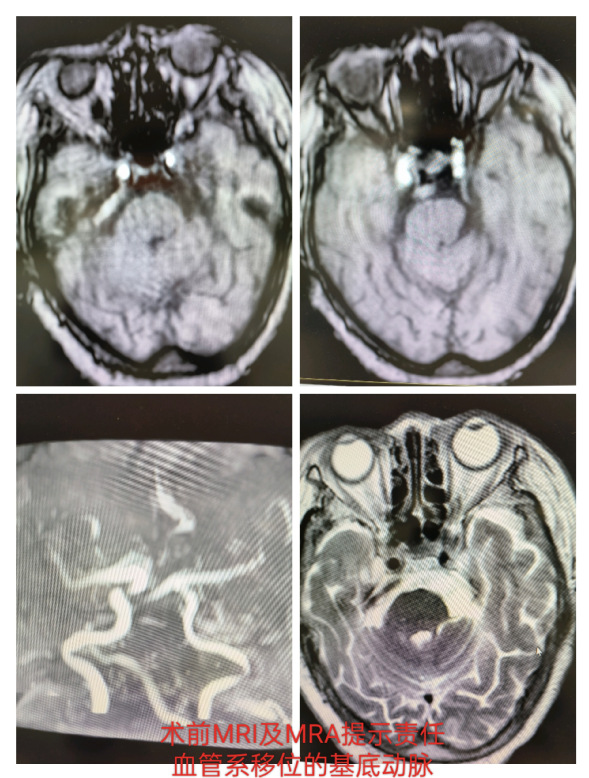

王云龙副主任医师根据患者的病情及身体状况为该患者制定了个体化的治疗方案,因患者年龄较高,经严格的药物治疗效果不佳,恐惧开颅手术对微血管减压术依从性较差,术前三叉神经MRI检查提示患者又是一例粗大的椎基底动脉移位压迫右侧三叉神经根,患者长期高血压脑动脉硬化,经颅行微血管减压将血管推离三叉神经根且悬吊难度大,老人家不愿意行选择性三叉神经感觉根切断术,综合以上因素为老人家制定经皮穿刺三叉神经半月结微球囊压迫术的手术方案。该术式属于神经外科介入手术,在C型臂或脑血管造影机或神经外科手术机器人的定位下进行,手术时间短,且具有微创、无血、恢复快的优点,面部仅仅一个针孔,术后无任何痕迹,且费用低,老人家欣然接受,患者基础疾病较多,经心内科、神经内科及麻醉科多学科会诊并调整到最佳状态后如期行手术治疗,经手术室麻醉科通力协作,手术过程顺利,用时25分钟,术后疗效立竿见影,疼痛完全消失,折磨患者20余年的三叉神经痛终于获得成功治愈,老人家特别开心笑的跟孩子一样,患者于术后第二日即康复出院。

术前三叉神经MRI提示基底动脉移位压迫左侧三叉神经根部